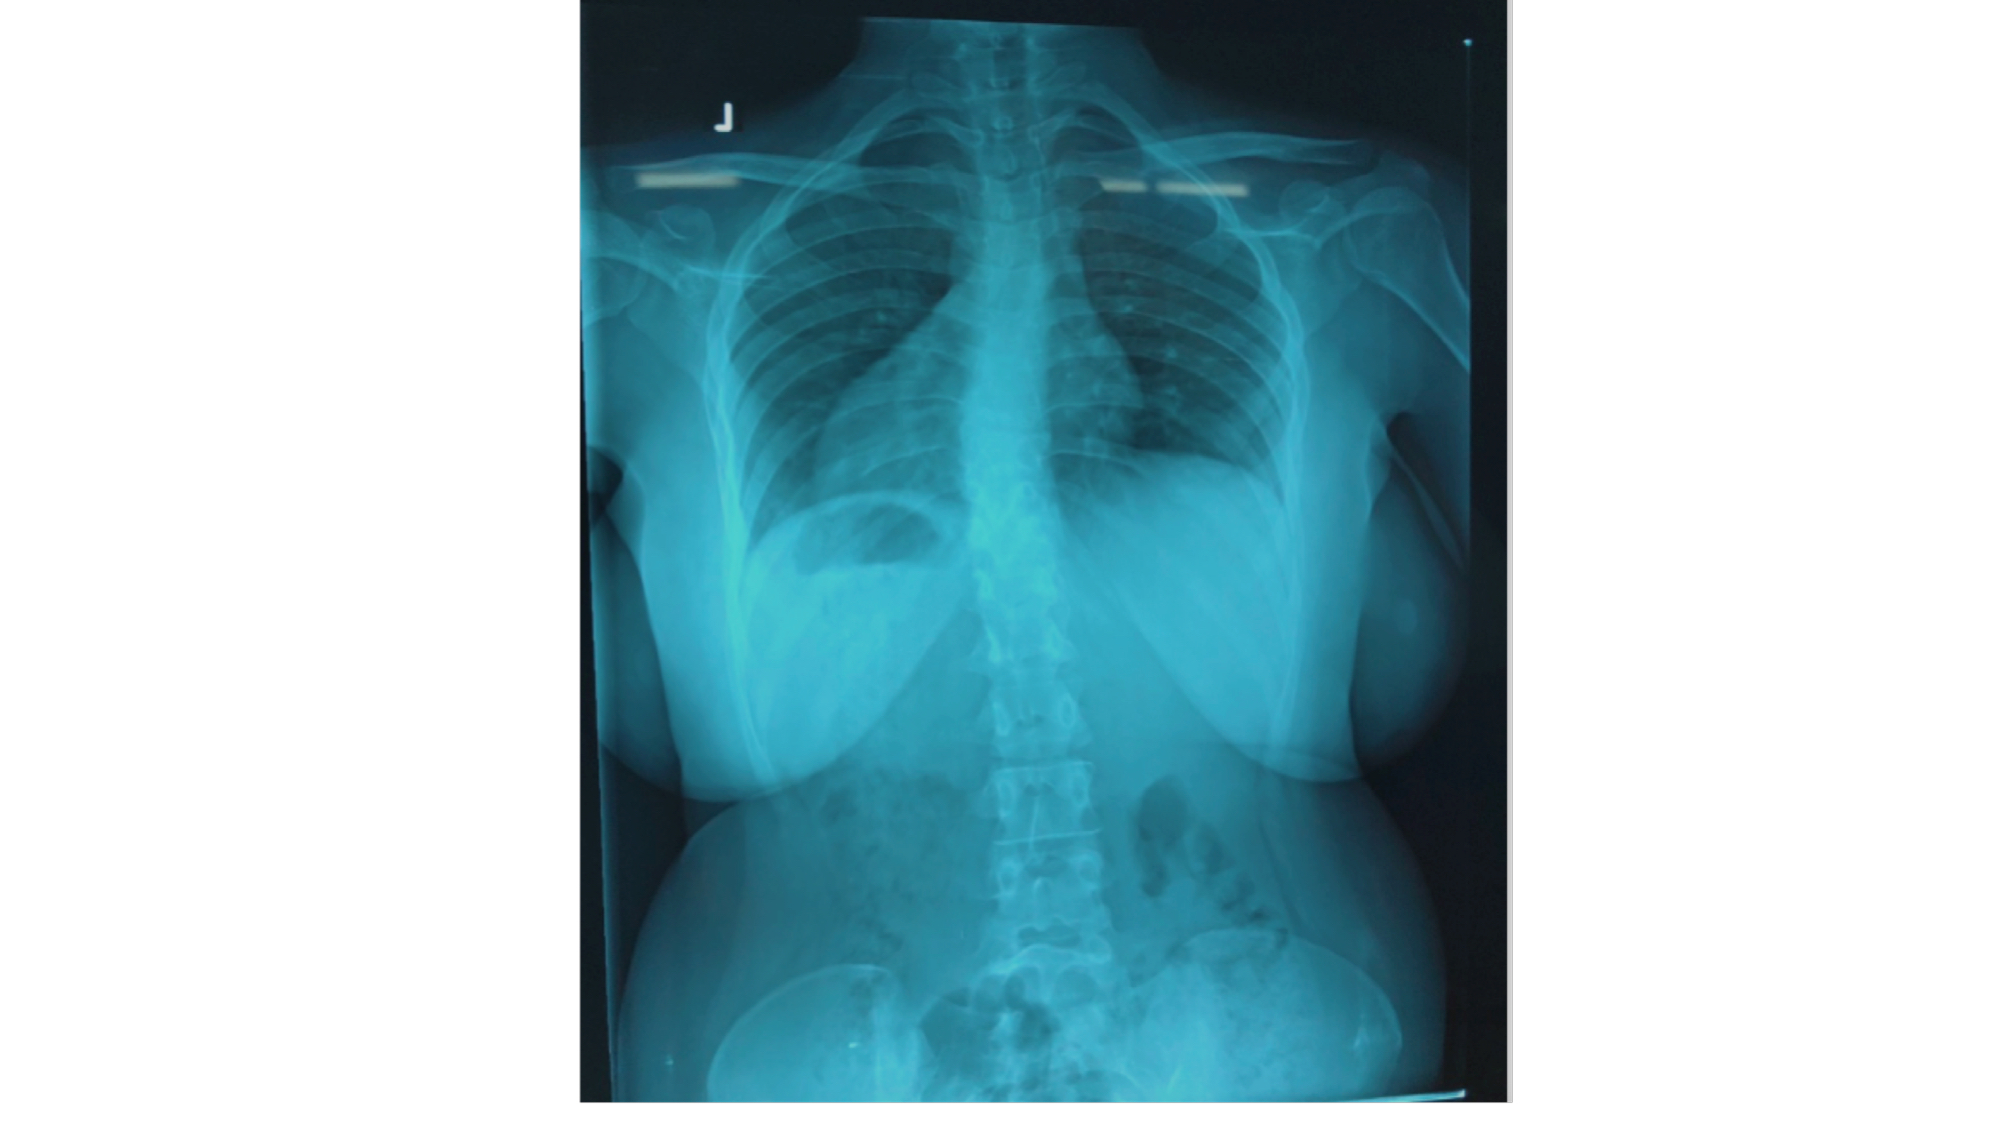

I was also able to meet the first two spine surgery fellows at AaBET. They are both neurosurgeons. The plan after next year is to alternate orthopedic with neurosurgery spine fellows. In addition to their teaching at AaBET, they are mentored by Dr Fasil Mesfin of Univeristy of Missouri, with whom they have weekly cases conferences. They were excited to show me two massive spine tumors they just operated on, one a giant, dumbbell shaped neurofibroma of the lower thoracic spine with bone involvement and preoperative paraparesis; the other a huge aneurysmal bone cyst of posterior lumbar element. Both needed pedicle screw instrumentation and big exposures. I am not a spine surgeon but the operative photos and postop xrays were very impressive.